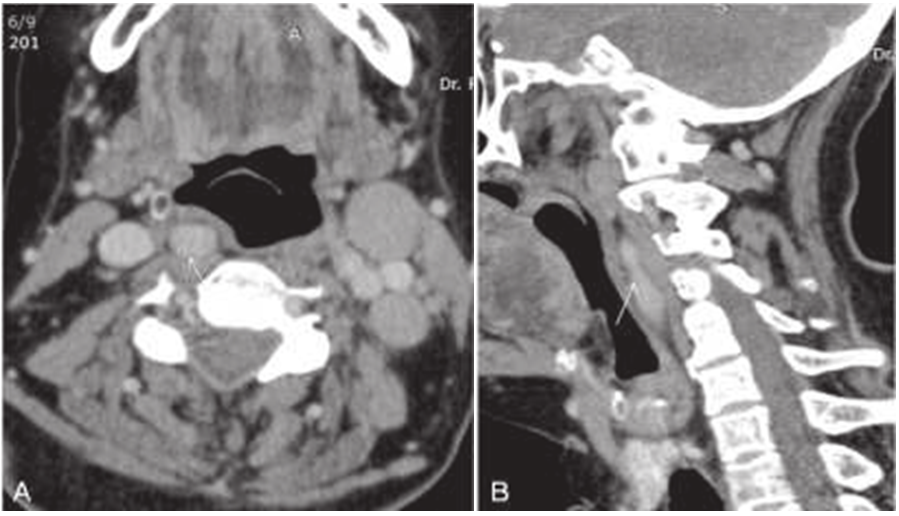

A 23 year old patient who is known case of Non-Hodgkins lymphoma on chemotherapy presenting with swelling on both sides of neck and there was a pulsating mass seen on left side in. The CECT scan of the patient was done and it showed (Figure 1 A&B) posterior pharyngial wall bulging a on right side (white arrow) with aberrant course of right ICA which shows medialisation. Note was also made of enlarged lymph nodes at station IIa and IIb on left side cervical regions. Diagnosis of medialisation of ICA on right side was made besides patient a known case of Non-Hodgkins lymphoma (Figure 1).

Figure 1 Known case of Hodgkin lymphoma a 23 year old female patient shows incidental findindg of bulge in the posterior oropharyngial wall clinically and CECT (Figure A &B)shows posterior pharngial wall bulging a on right side (white arrow) with aberrant course of right ICA which shows medialisation.note is made of enlarged lymph nodes at station IIa and IIb on left side cervical regions.